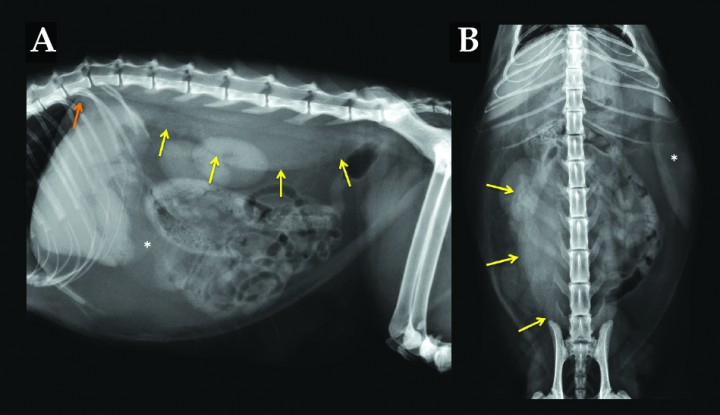

Se realizan radiografías de abdomen lateral (L) y ventrodorsal (Fig. 1) para investigar posibles causas del dolor abdominal y la fiebre asociada.

<p>(A) Radiografía lateral y (B) ventrodorsal de abdomen de un gato que se presenta con dolor abdominal.</p>

(A) Radiografía lateral y (B) ventrodorsal de abdomen de un gato que se presenta con dolor abdominal.

El paciente presenta buena definición de serosas gracias al abundante tejido adiposo intraabdominal (Fig. 2). El tracto gastrointestinal tiene un patrón de contenido gaseoso-mucoso, con heces formadas en intestino grueso sin tramos de distensión patológica. El bazo presenta un incremento marcado de tamaño, con bordes regulares redondeados, silueta y opacidad homogéneas en la pared izquierda del abdomen (asterisco), ocupando una posición más ventral de lo esperado debido a su incremento de tamaño.

<p>Mismas radiografías que en la Figura 1. Las flechas amarillas demarcan la extensión de la opacidad tejido blando asociada a la musculatura espinal desde el nivel del ilion derecho hasta la parte ventral de T12 (flecha naranja), desplazando el riñón derecho ventrolateralmente. El bazo (*) presenta un marcado aumento de tamaño con bordes regulares y homogéneos.</p>

Mismas radiografías que en la Figura 1. Las flechas amarillas demarcan la extensión de la opacidad tejido blando asociada a la musculatura espinal desde el nivel del ilion derecho hasta la parte ventral de T12 (flecha naranja), desplazando el riñón derecho ventrolateralmente. El bazo (*) presenta un marcado aumento de tamaño con bordes regulares y homogéneos.

Podemos apreciar una opacidad tejido blando con bordes homogéneos y bien definidos lateral y ventralmente, con signo de silueta positivo asociada al dorso de la cavidad abdominal (flechas amarillas), que desplaza ambos riñones ventralmente (el derecho también lo desplaza lateralmente, visible en la proyección VD), así como el borde caudodorsal de los lóbulos pulmonares caudales (flecha naranja). La opacidad se extiende por la porción derecha del tejido blando paraespinal desde el nivel de la T12 hasta L7. No se aprecian signos de reactividad ósea asociados a la opacidad tejido blando. El resto de la exploración no presenta alteraciones significativas.